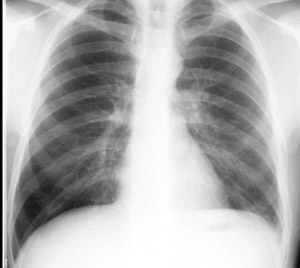

• Loss of silhouette. In the images below note lack of identifiable left diaphragm before and visible diaphragm after clearance of fluid (Silhouette sign principle)

After thoracentesis

Left diaphragm is seen clearly.